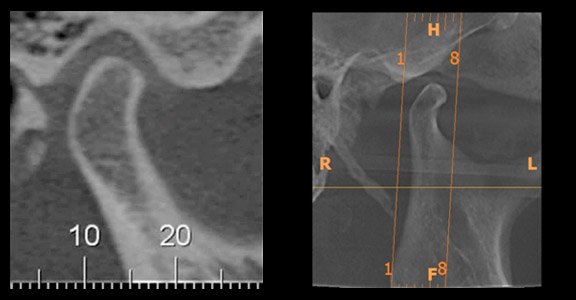

Diferentemente das radiografias convencionais, que projetam em um só plano todas as estruturas atravessadas pelos raios-x, a TC evidencia as relações estruturais em profundidade, mostrando imagens em “fatias” do corpo humano. A TC permite enxergar todas as estruturas em camadas, principalmente os tecidos mineralizados, com uma definição admirável, permitindo a delimitação de irregularidades tridimensionalmente.

Assim sendo, apesar de os métodos radiográficos permitirem somente a observação dos tecidos duros desta articulação, a avaliação tomográfica já é suficiente para auxiliar o diagnóstico final de uma série de condições patológicas tais como: processos degenerativos da cabeça da mandíbula, fraturas, sua dinâmica de movimentos (tomadas em boca aberta e boca fechada), anquilose e até mesmo em neoplasias (extremamente raras na ATM).